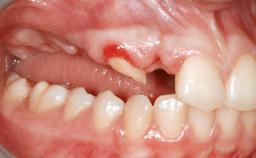

An 18-year-old man was referred for implant therapy in the posterior mandible to the Department of Oral Surgery and Stomatology (University of Bern, Switzerland). He was healthy and did not smoke. Tooth 35 was congenitally missing, involving a single-tooth edentulous space that offered an adequate mesiodistal dimension for implant placement but exhibited a typical pattern of buccal flattening. A panoramic radiograph was obtained, which revealed a sufficient vertical bone height above the mandibular canal and a normal bone structure in the edentulous area.